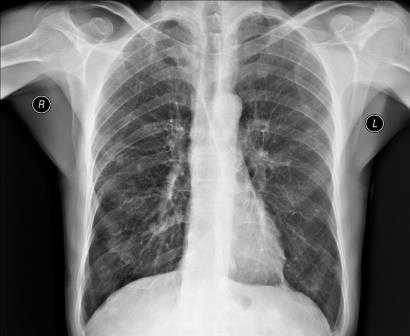

Нормальная картина

В норме на снимках, выполненных в заднепередней проекции, ширина грудной клетки по меньшей мере в 2 раза превышает поперечный размер сердца. В то же время в переднезадней проекции относительные размеры и положение сердца могут быть другими; возможно усиление тени сердца и дуги аорты. Когда исследование проводится с контрольной целью, рентгенограммы грудной клетки должны подтверждать правильное положение катетеров и водителей ритма.

Изменение формы сердца обычно заключается в увеличении левого или правого желудочка, левого предсердия или даже нескольких полостей. При увеличении левого желудочка в заднепередней проекции левая граница сердца становится круглой и выпуклой с боковым расширением в своей нижней части, а в боковой проекции определяется выбухание левого желудочка кзади. При увеличении правого желудочка в заднепередней проекции наблюдается вторичное изменение левой границы сердца за счет расширения тени легочной артерии, а в боковой - расширение тени выносящего тракта правого желудочка. При увеличении левого предсердия его плотность на рентгенограмме в заднепередней проекции увеличивается вдвое, левая граница сердца сглаживается, левый главный бронх смещается кверху. В редких случаях правая граница сердца над проекцией правого желудочка расширяется кнаружи. В боковой проекции определяется выбухание левого предсердия кзади. Начальными признаками застоя в малом круге кровообращения на снимках, сделанных в заднепередней проекции, являются расширение тени легочных вен в верхнебоковой части корней легких и сосудистые тени, расположенные горизонтально вдоль нижней части правой границы сердца. Хроническая легочная венозная гипертензия приводит к формированию рисунка по типу оленьих рогов (из расширенных верхних и нормальных или суженных нижних легочных вен). При остром отеке легких увеличение плотности в центре легочных полей может по форме напоминать бабочку. Интерстициальный отек легких может напоминать снежные хлопья на фоне легочных полей.

Результаты диагностик и расшифровка рентген-снимков грудной клетки

После получения изображения рентгенолог делает заключение и краткое описание снимка для врача, направившего пациента на обследование. В записи указывается, как расположено сердце, его размер (увеличенный или нормальный), какова его паренхима. Кроме того описывается состояние и остальных внутренних органов грудной клетки - легких, бронхов, сосудов и лимфатических узлов. Если снимок показал наличие посторонних предметов, затемнений или новообразований, это также отражается в заключении рентгенолога.

Во время расшифровки полученного рентгеновского снимка, прежде всего, оценивается качество изображения, а значит, и насколько правильно осуществлена процедура. Если рентгенография была сделана в неверной проекции и снимок имеет неточности, то заключение на его основании сделать достаточно сложно. При рентгене легких, например, оценивается размер легких, их форма, структура тканей и легочных полей, состояние воздушности и расположение внутренних органов.

Если у пациента пневмония, на снимке будут видны ярко выраженные отклонения от нормы - интенсивные дополнительные ткани как на прямой, так и на боковой рентгенограмме. Присутствие на снимке особой прикорневой формы, напоминающей по виду крылья бабочки, говорит о венозном застое в области малого круга. На отечность легочной ткани будут указывать неравномерные хлопьевидные затемнения на изображении.